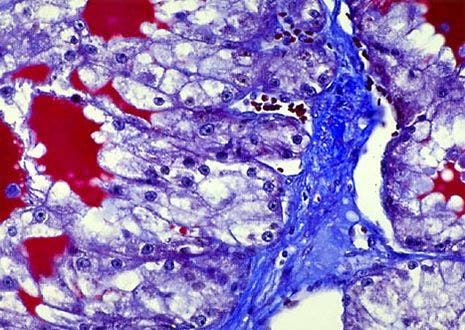

Kidney Stained Tissue

The kidney is one of the major homeostatic devices of the body. The organ maintains water balance and expels metabolic wastes in vertebrates and some invertebrates. In primal and embryonic organisms, kidneys have sets of specialized tubules that empty into collecting ducts that pass urine into a primitive bladder.